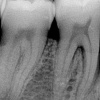

Krooniline parodontiit

Krooniline parodontiit on mikroobide poolt põhjustatud hammaste tugikudede põletik, mille tulemusena tekib progresseeruv alveolaarluu (nähtav röntgenograamil) ja periodontaalligamendi destruktsioon, igemetaskute moodustumine, igeme retsessioon või mõlemad kahjustused kombineeritult. Krooniline parodontiit on...